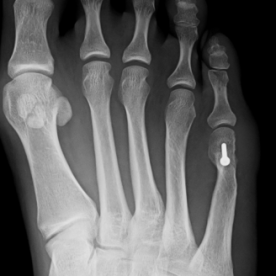

11) Hallux rigidus

Arthrose des Großzehengrundgelenkes. Im Frühstadium erfolgt eine konservative Therapie, im fortgeschrittenen Stadium ist eher eine operative Therapie angezeigt. Sie umfasst die Abtragung von Knochenausziehungen, ggf. ist eine prothetische Versorgung oder eine Versteifung des Großzehengrundgelenkes notwendig.